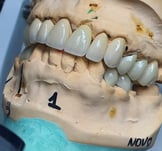

Coroa sobre Implante aparafusada em Modelo impresso. zirconia/cerâmica

Protese Protocolo finalizada, seguindo etapas de seleçao de cor de dentes e gengiva e provas estéticas, sempre com a participaçao do paciente em todo o processo.

Fase de produção laboratórial das coroas sobre dentes e implantes e facetas de porcelanas personalizadas

Em um bom laboratório, essas peças são confeccionadas com precisão, utilizando tecnologia avançada para garantir o ajuste perfeito e a estética desejada.